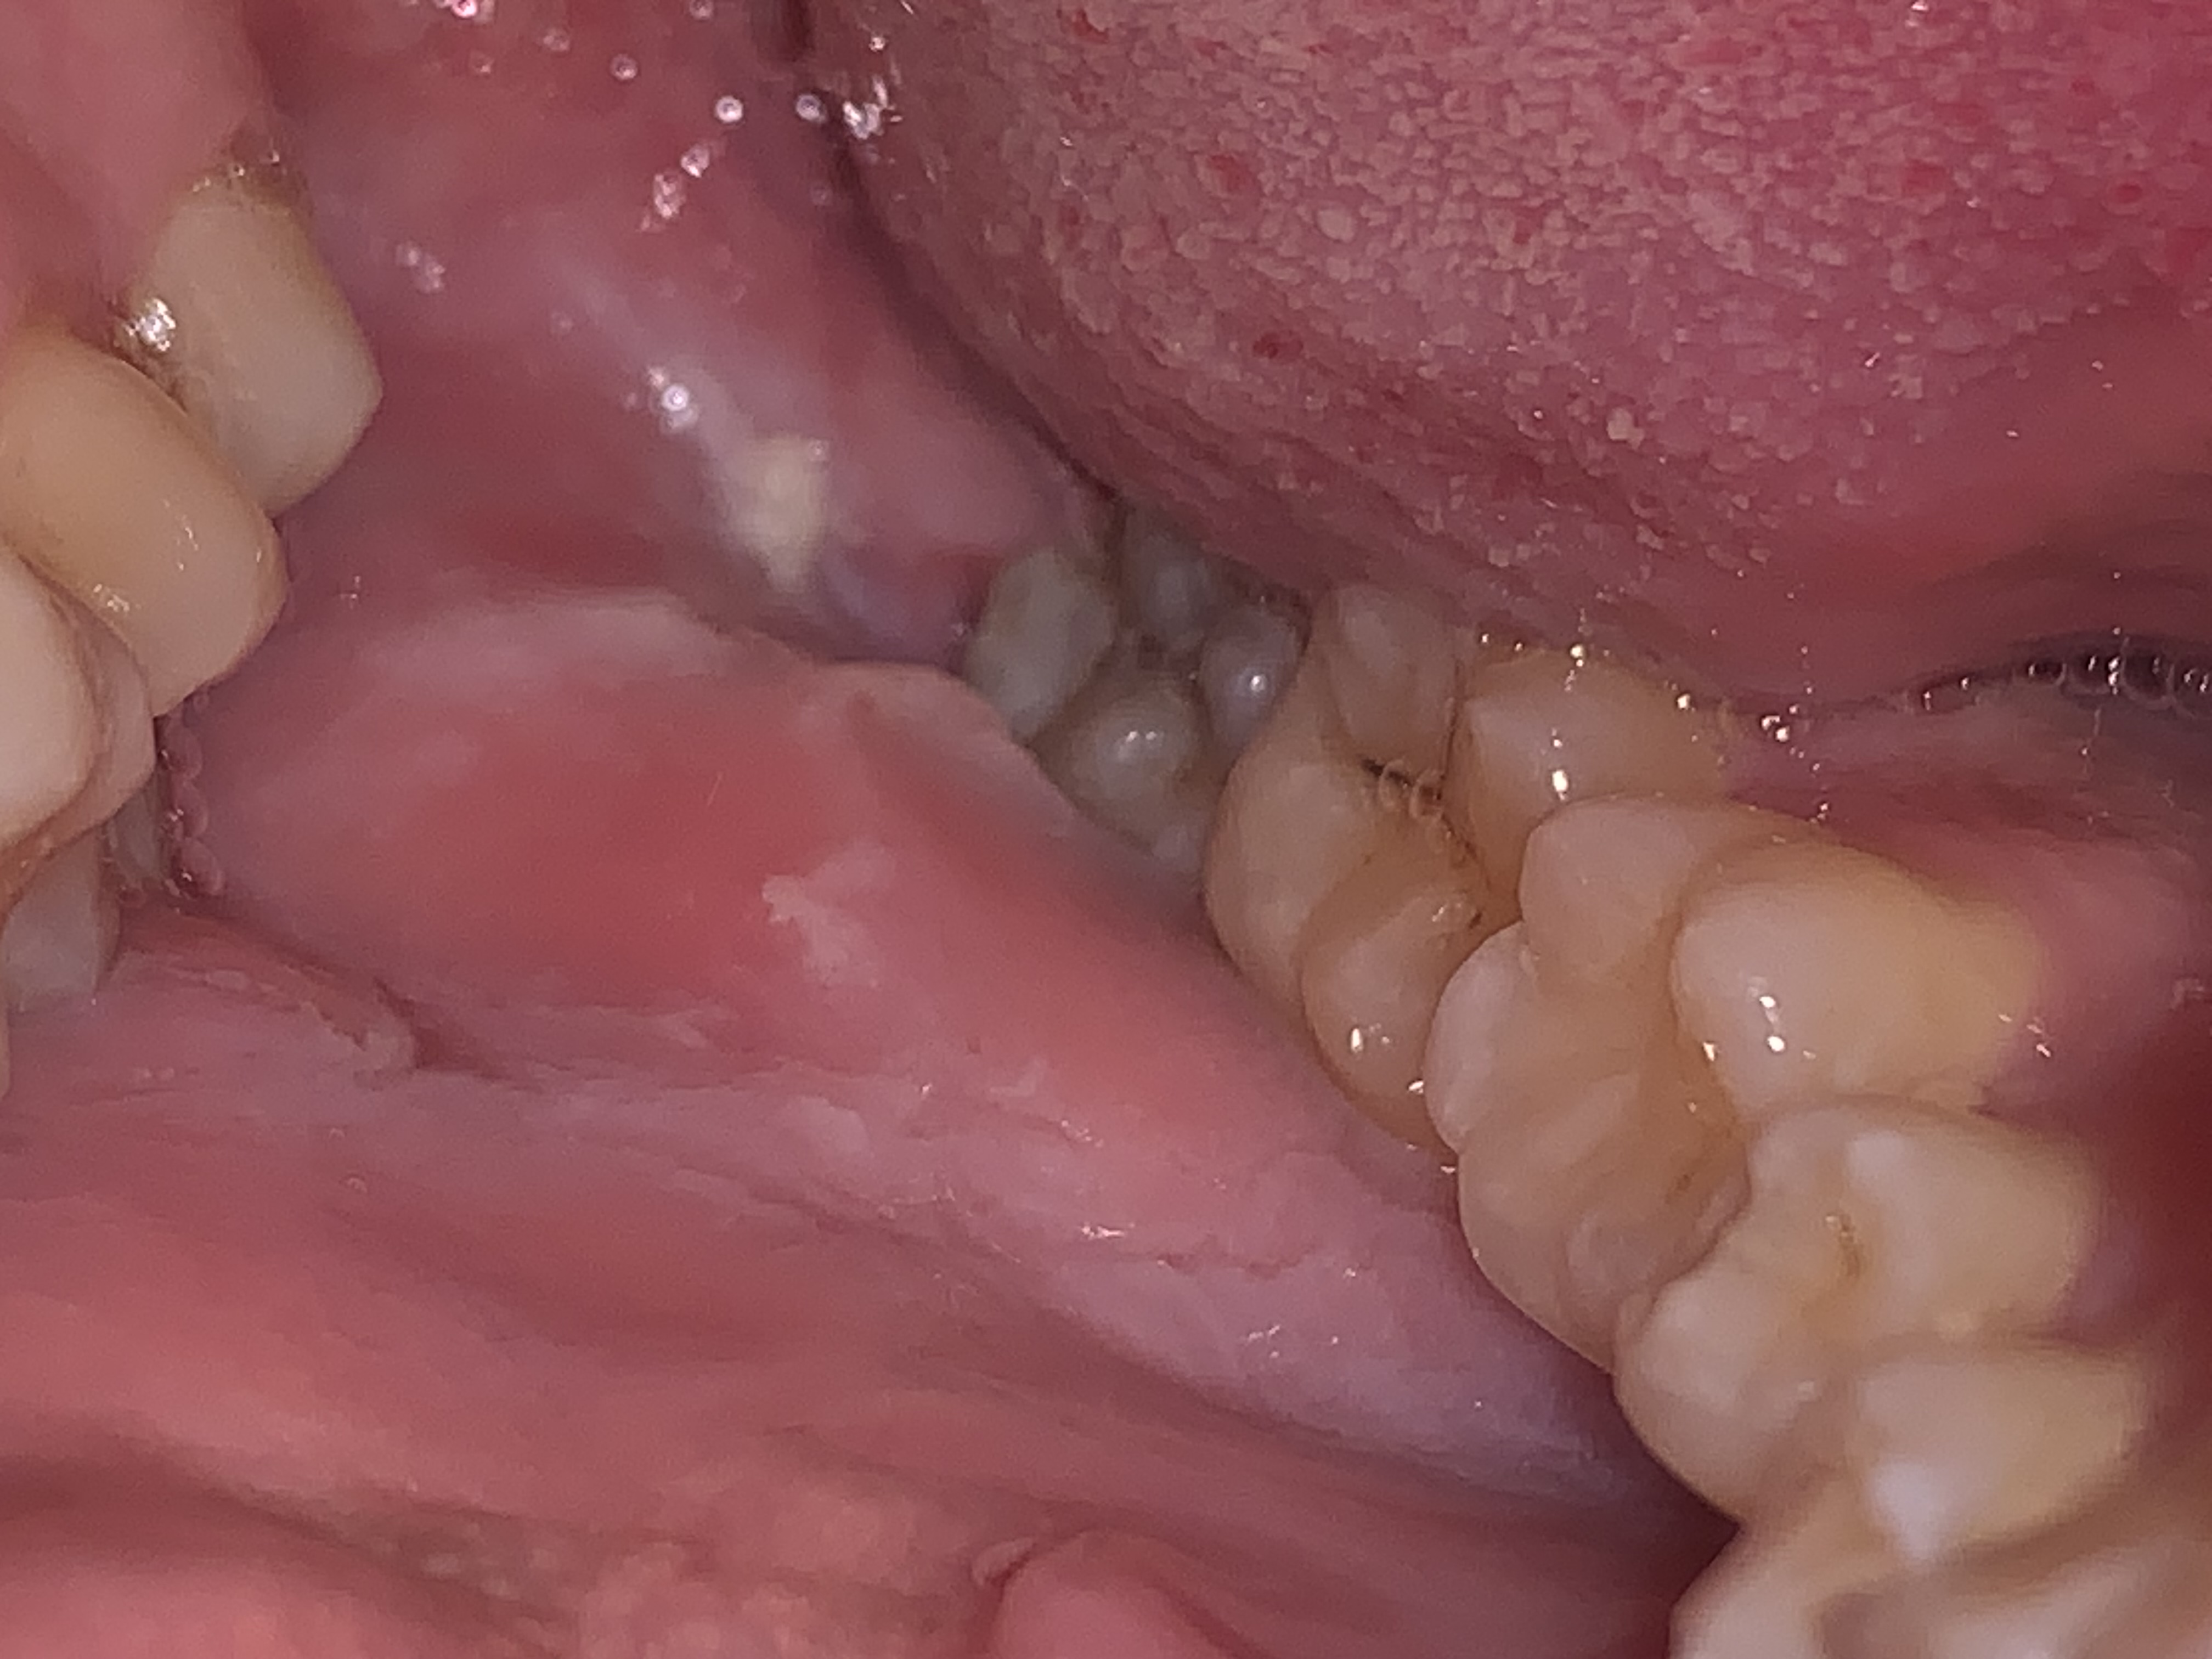

Salve, sono un ragazzo immunosoppresso in quanto ho ricevuto un trapianto di rene più di un anno fa. Da circa 2–3 settimane ho notato all’interno delle guance delle formazioni molli di colore bianco. Scrivo qui per chiedere altri pareri.

Mi sono fatto visitare dal mio dentista e non mi ha ancora dato una vera diagnosi, ma solo fissato un altro appuntamento a un mese di distanza per vedere se la situazione rimarrà tale o si risolverà da sola. Mi ha comunque controllato il morso, credo per verificare se i denti sfregano o mordono la guancia.

Ha detto anche che vorrebbe rimuovermi il dente del giudizio, che potrebbe sfregare e creare questo problema, ma solo nella sua zona e non a livello delle guance. La foto risale a più di due settimane fa, anche se la situazione risulta più o meno la stessa.

Qualora dovesse permanere è bene ottenere una diagnosi certa prima di togliere il dente del giudizio.